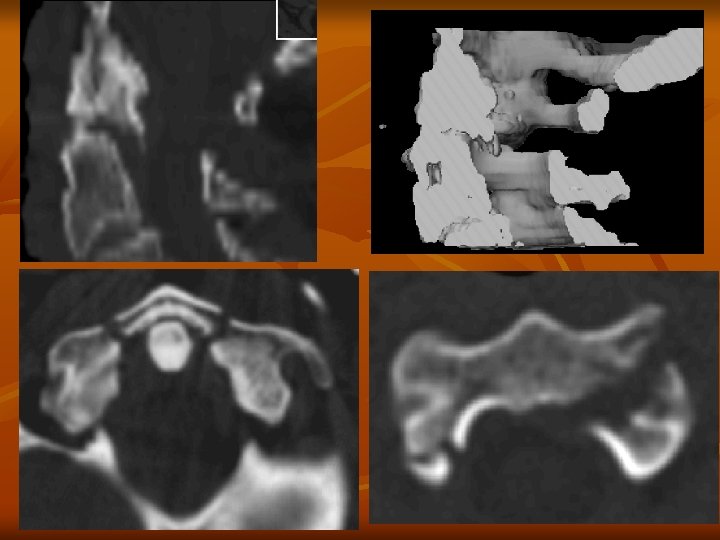

Fejlődési rendellenességek n Csontérintettség n spondylolysis

Spondylolysis, Spondylolisthesis n n n Spondylolysis az un pars intrarticularison képződő defektust jelöli Stressztörés eredménye általában Spondylolysis fájdalommal és gerinc instabilitással járhat Spondylolysis következtében spondylolisthesis alakulhat ki. Spondylolisthesisnél két csigolya között elcsúszás következik be. A gerinc deformálodik és a foramenek beszűkűlnek

CT